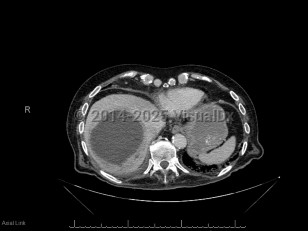

Pyogenic liver abscess

A pyogenic liver abscess is a collection of pus in the liver as the result of bacterial (or rarely fungal) infection.

Many organisms can cause a pyogenic liver abscess, and many abscesses are polymicrobial. Common pathogens include Escherichia coli and Klebsiella species (including the hypermucoid strains of Klebsiella pneumoniae that are a major cause of liver abscess in Asia). Anaerobic organisms are frequently involved, and gram-positive organisms including Streptococcus species and Staphylococcus aureus can also cause abscesses. Candida species may also be involved. Clostridium perfringens liver abscesses can cause hemolysis.